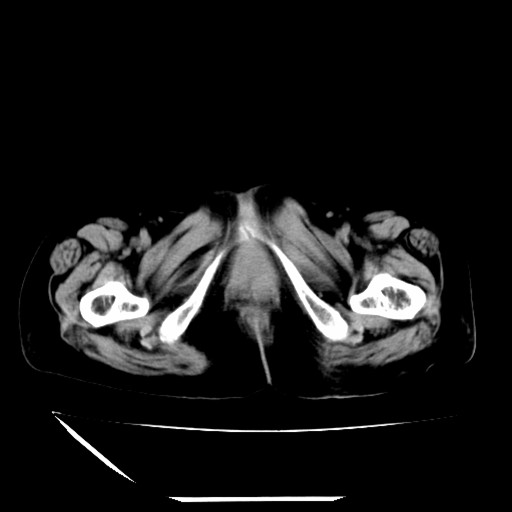

标题: CT16840:女-63岁,下腹部疼痛,

道格拉斯窝内少量积液。

盆腔少量积液   支持

支持 阑尾炎,盆腔少量积液。